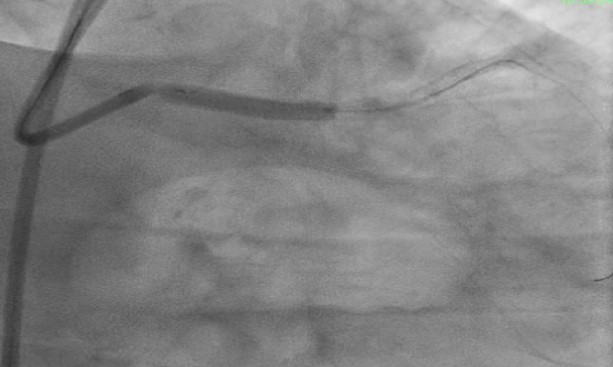

1) Proximal Left Anterior Descending artery's pre analysis done with OCT.2) Calcium arc on OCT displayed as 360 degrees with 800 micron thickness and length greater then 5mm with minimum Lumen Area of 1.83mm3) Intravascular Lithotripsy performed with focus on proximal Left Anterior Descending Artery4) Post Intravascular Lithotripsy procedure, Optical Coherence Tomography was performed5) The lumen gain obtained post procedure was equivalent to 5.24mm6) Stenting done7) LCX ostium with tight lesion with heavy calcification pre dilated with NC balloon and two stents placed.